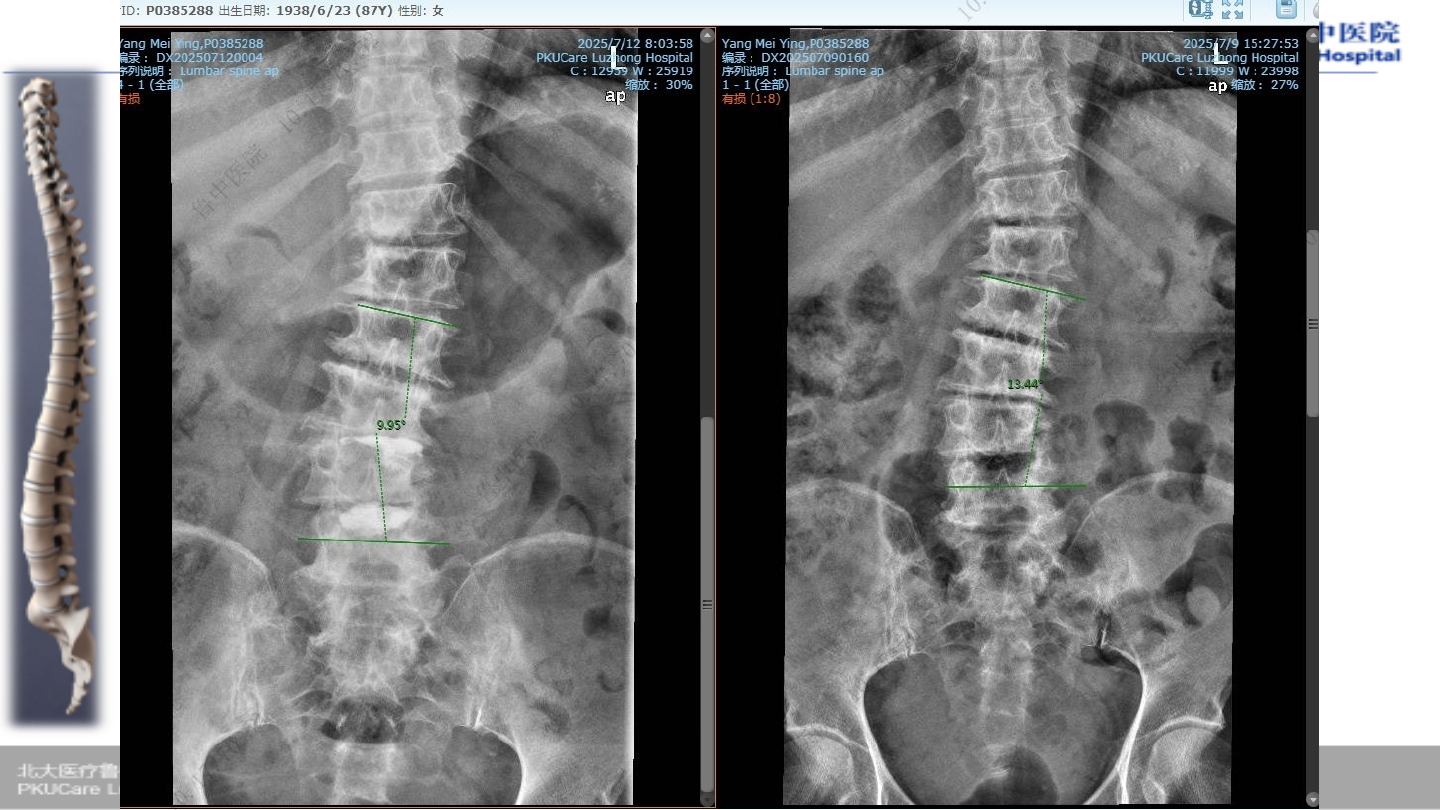

术前

X-ray